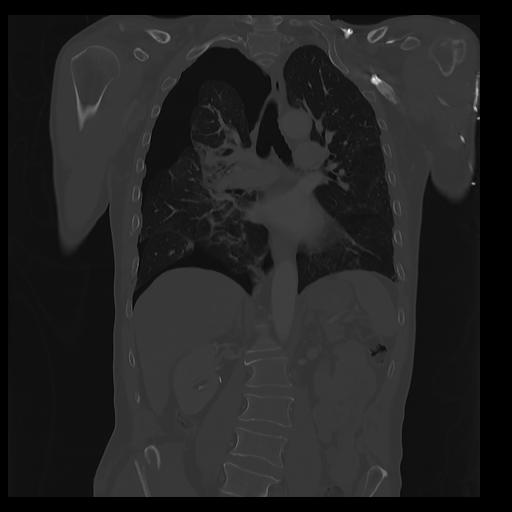

32 PULMON,CE,Coronal,3.000,PULMON,Coronal,